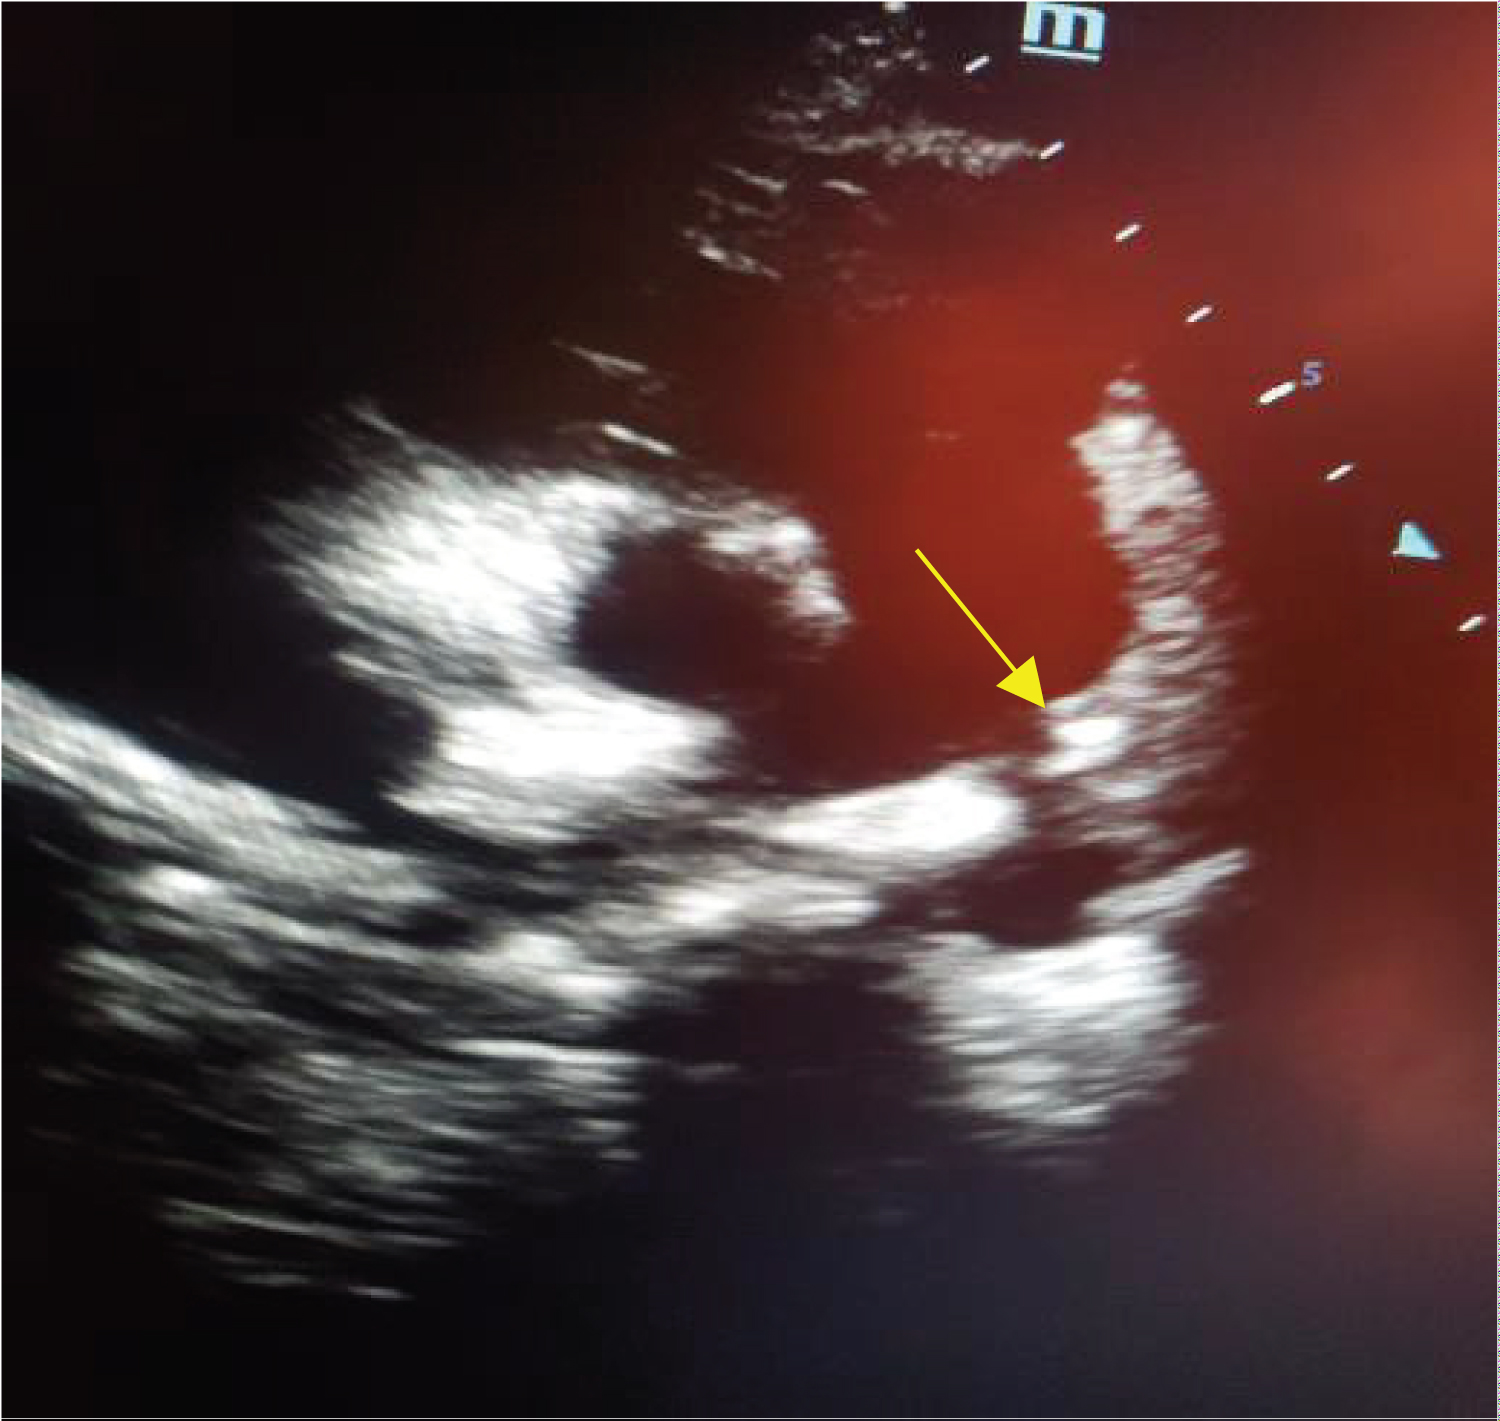

The patient remained in the intensive care unit (ICU) post-surgery for 4 days, which passed smoothly except for two attacks of staring for a few seconds which diagnosed later by EEG, abnormal epileptic attacks. Post-operative echocardiography showed a mild residual shunt through the closed PDA, a residual mild regurgitation, and a mild aortic regurgitation. Right ventricular pressure elevated with flattening of IVS (D-sign + VE) signs of severe pulmonary hypertension. No pericardial effusion (Figure 2).

Figure 2: Echocardiography post-operative demonstrate the closed PDA and pericardial patch with residual shunt (the arrow), Dr. H. Al-Fakih, Cardiologist MD. View Figure 2